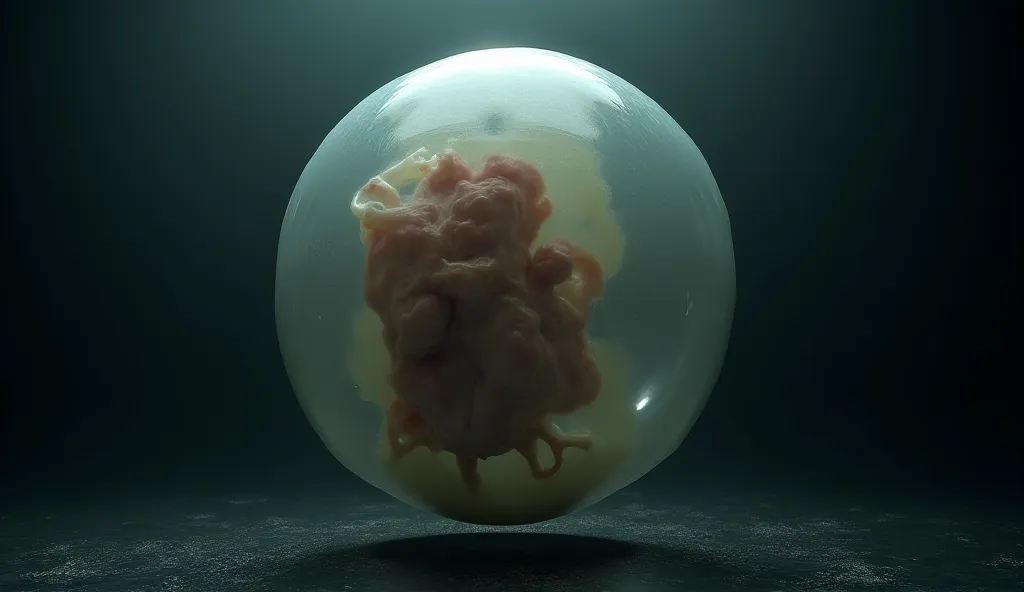

Image of a 10-week-old embryo in a uterus, captura, maternal photography 4 k

Image of a 10-week-old embryo in a uterus, captura, maternal photography 4 k, high quality scan, extremely high quality scan, high resolution scan,, video still, feto, webcam footage, high resolution scan, Escaneo profesional de alta calidad, metraje realista. hiper realista

Image of a 10-week-old embryo in a uterus